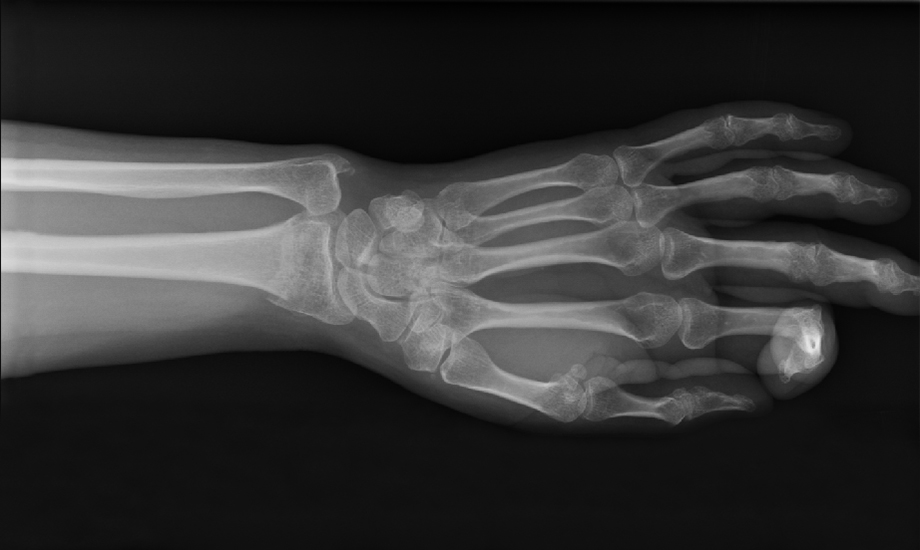

The Five-Finger Mantra KNOWLEDGE The cure for a broken bone is complete immobilization while the body miraculously heals itself.  Slowly, spring began to arrive and by the end of April 2020, the…

PART ONE – Snowboarding Three days after the World Health Organization announced the coronavirus pandemic, Saturday morning dawned with a layer of fresh powder on the mountain. Justin and I were on…